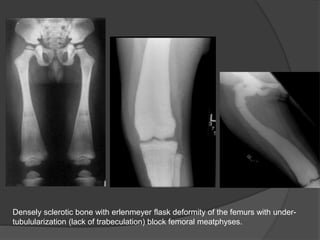

Densely sclerotic bone with erlenmeyer flask deformity of the femurs with under-

tubulularization (lack of trabeculation) block femoral meatphyses.